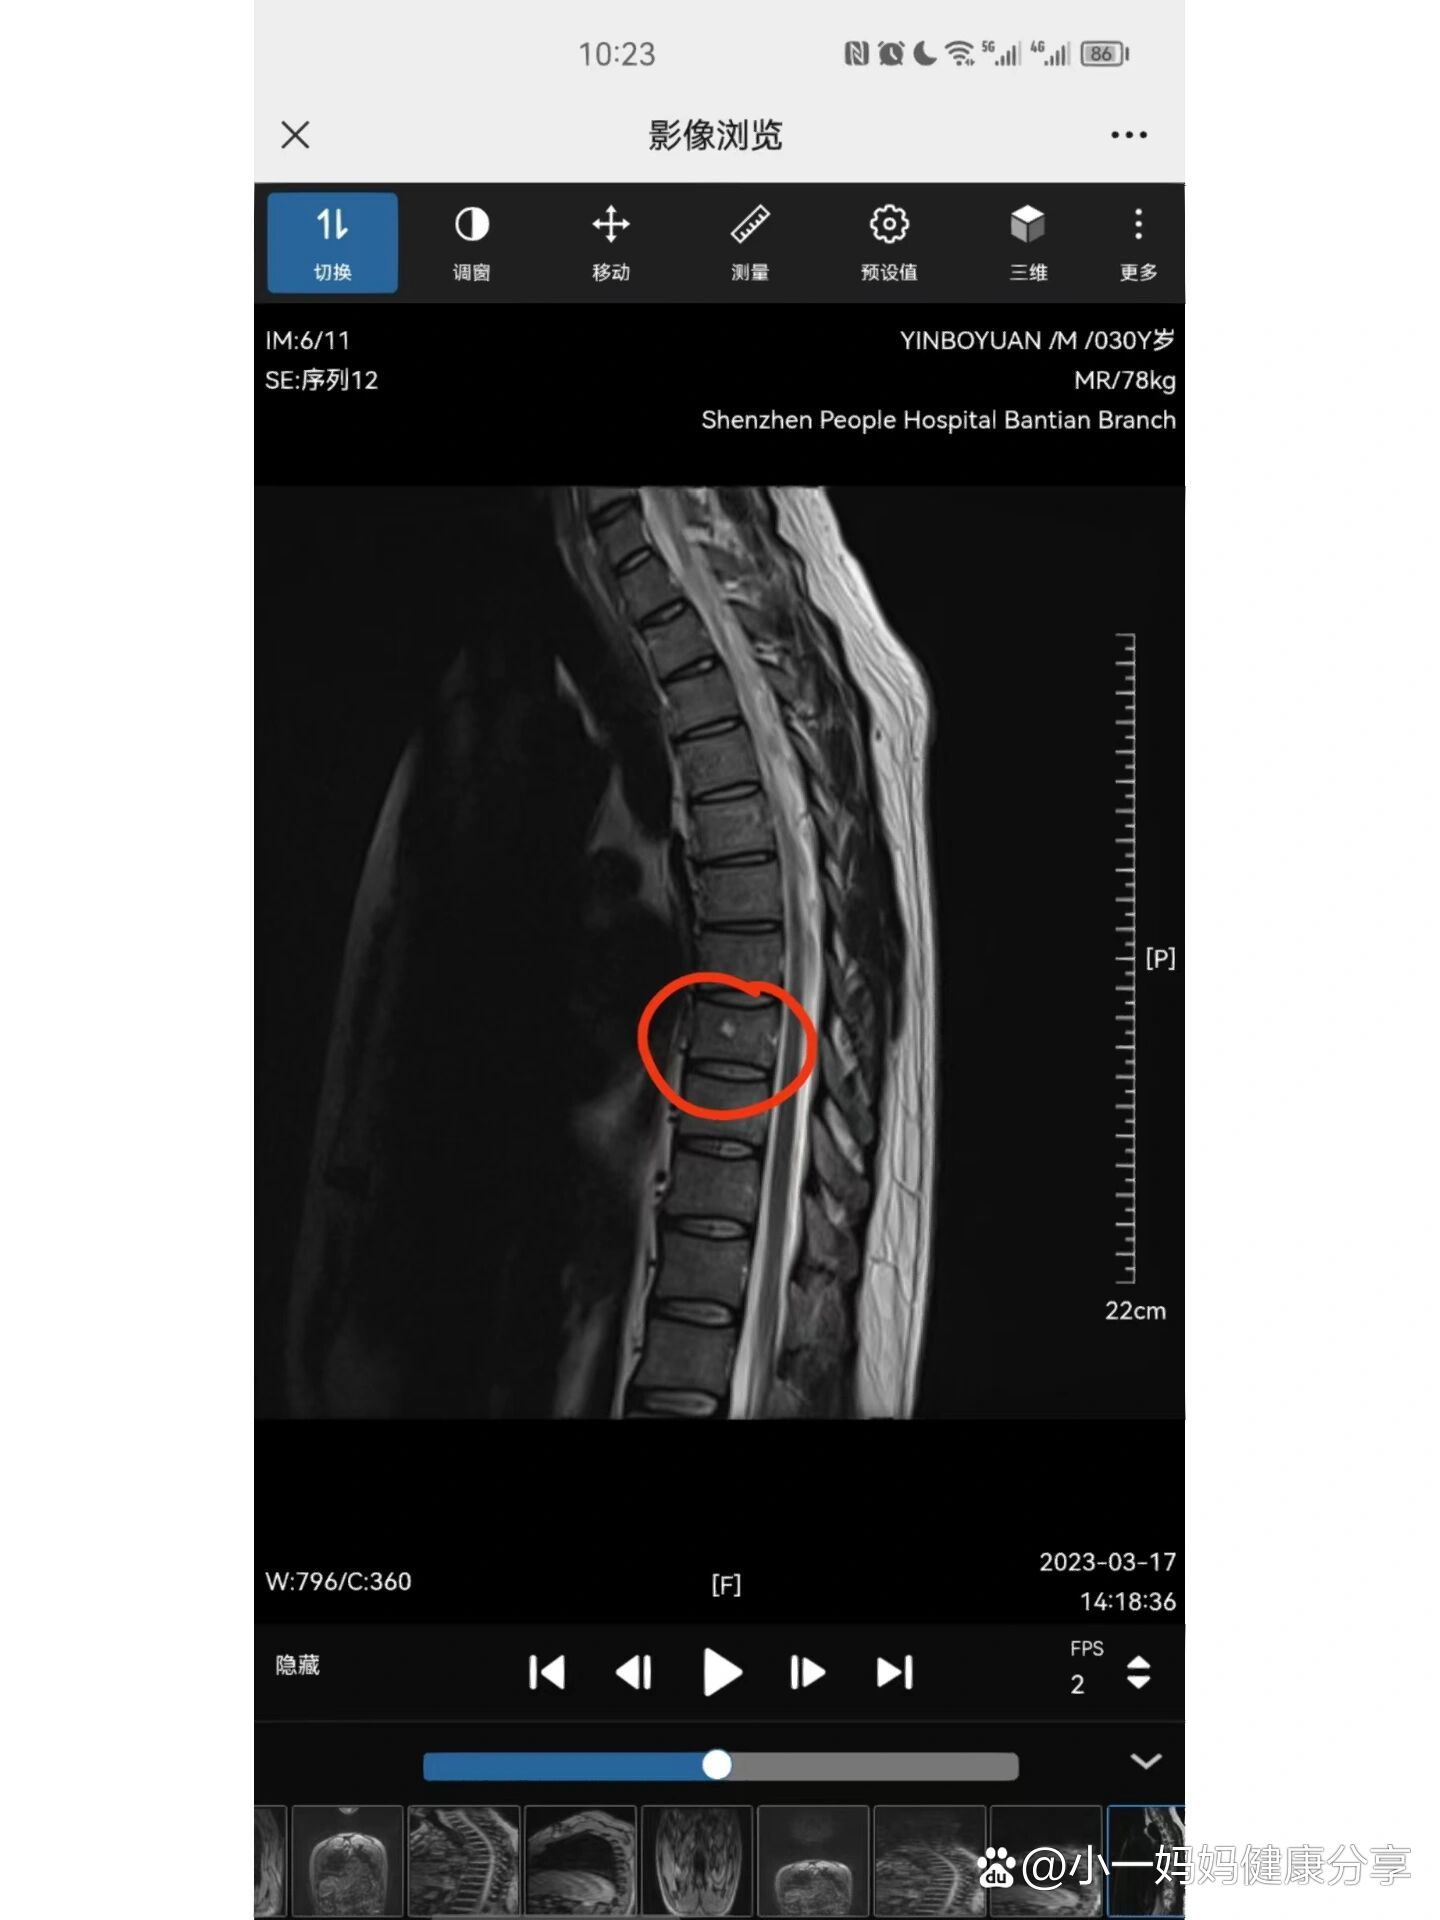

p>后背疼 mri胸椎血管瘤 br>书接上文 br>后背痛经过三次按摩理疗

图片尺寸1440x1920